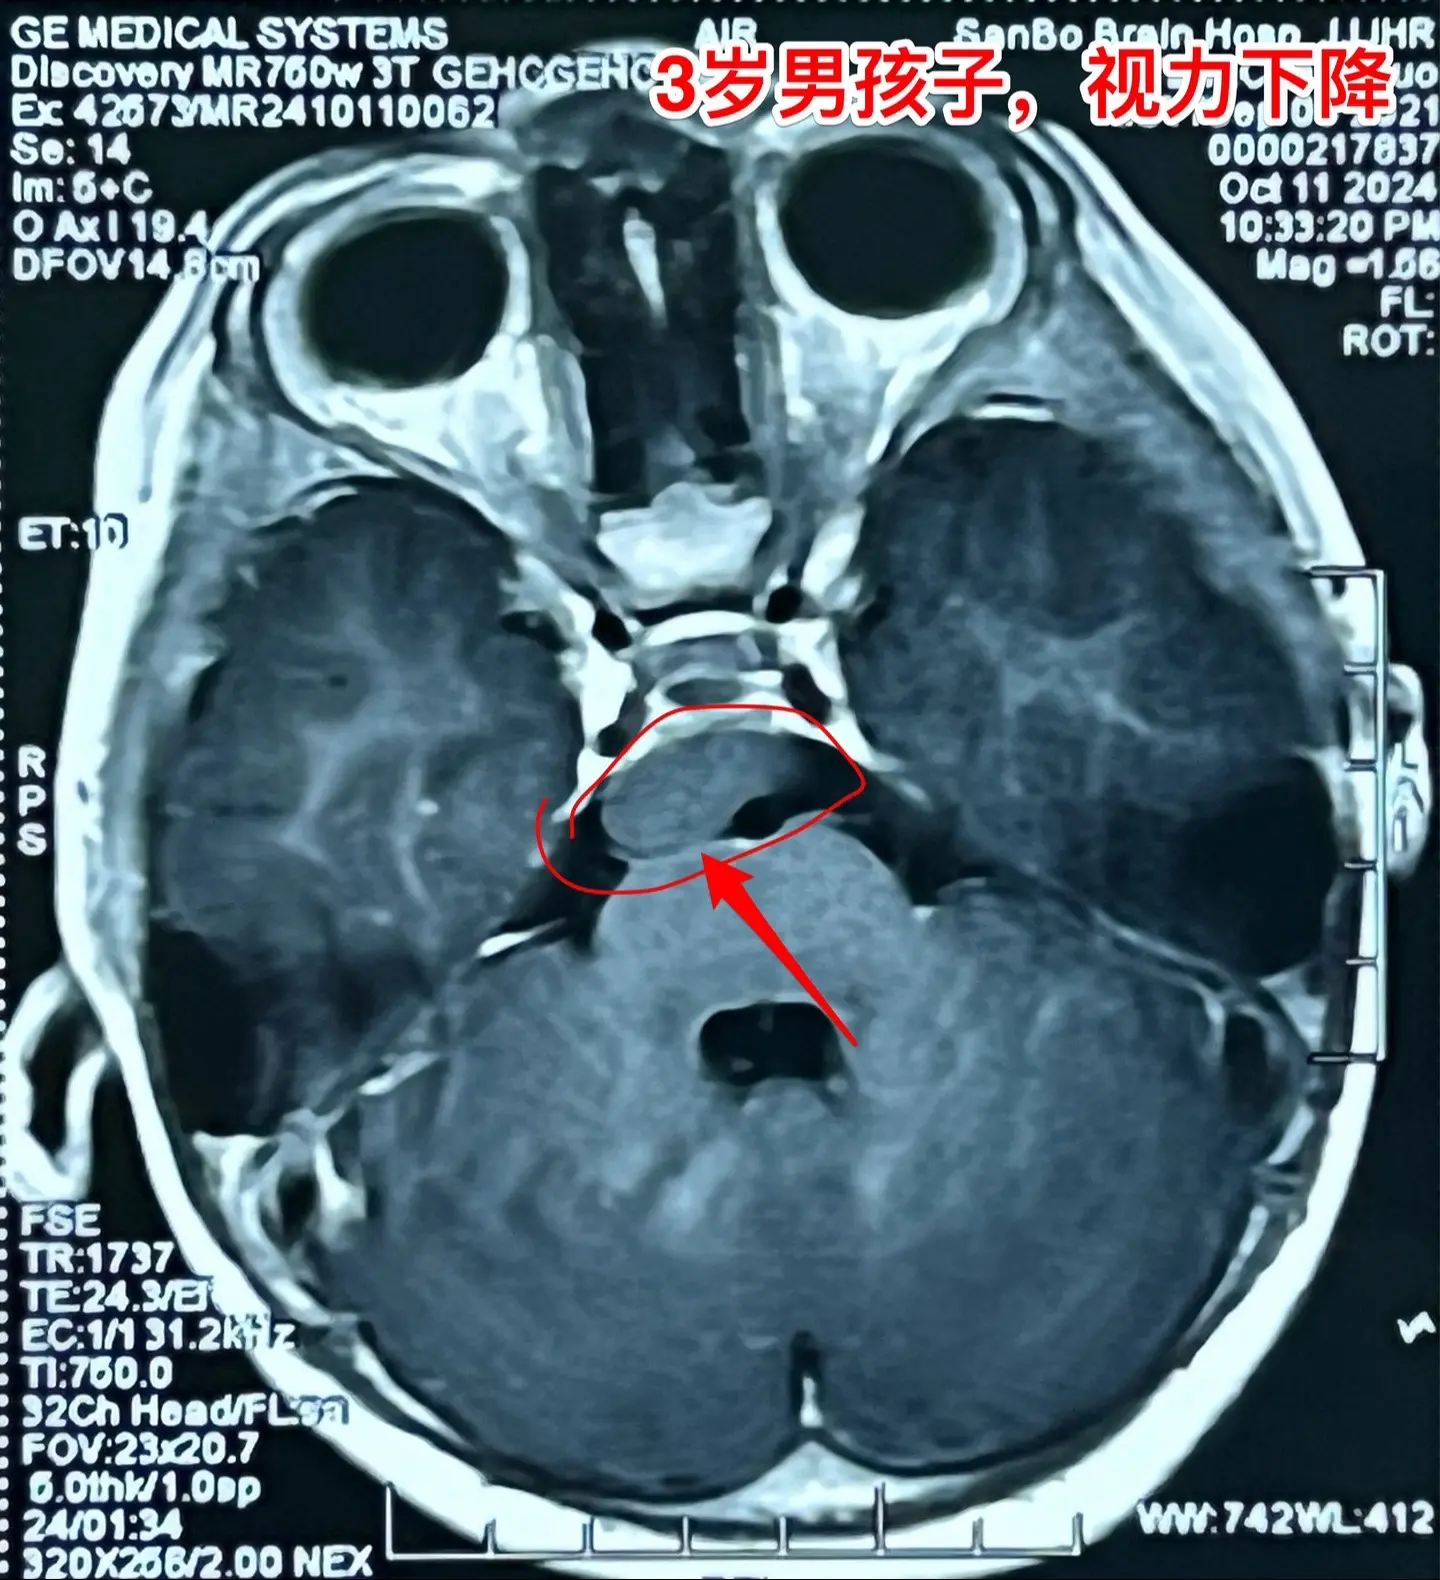

四岁男孩子右侧上下肢有点偏瘫症状!四岁苏州市男孩子出现视力下降、左侧眼...